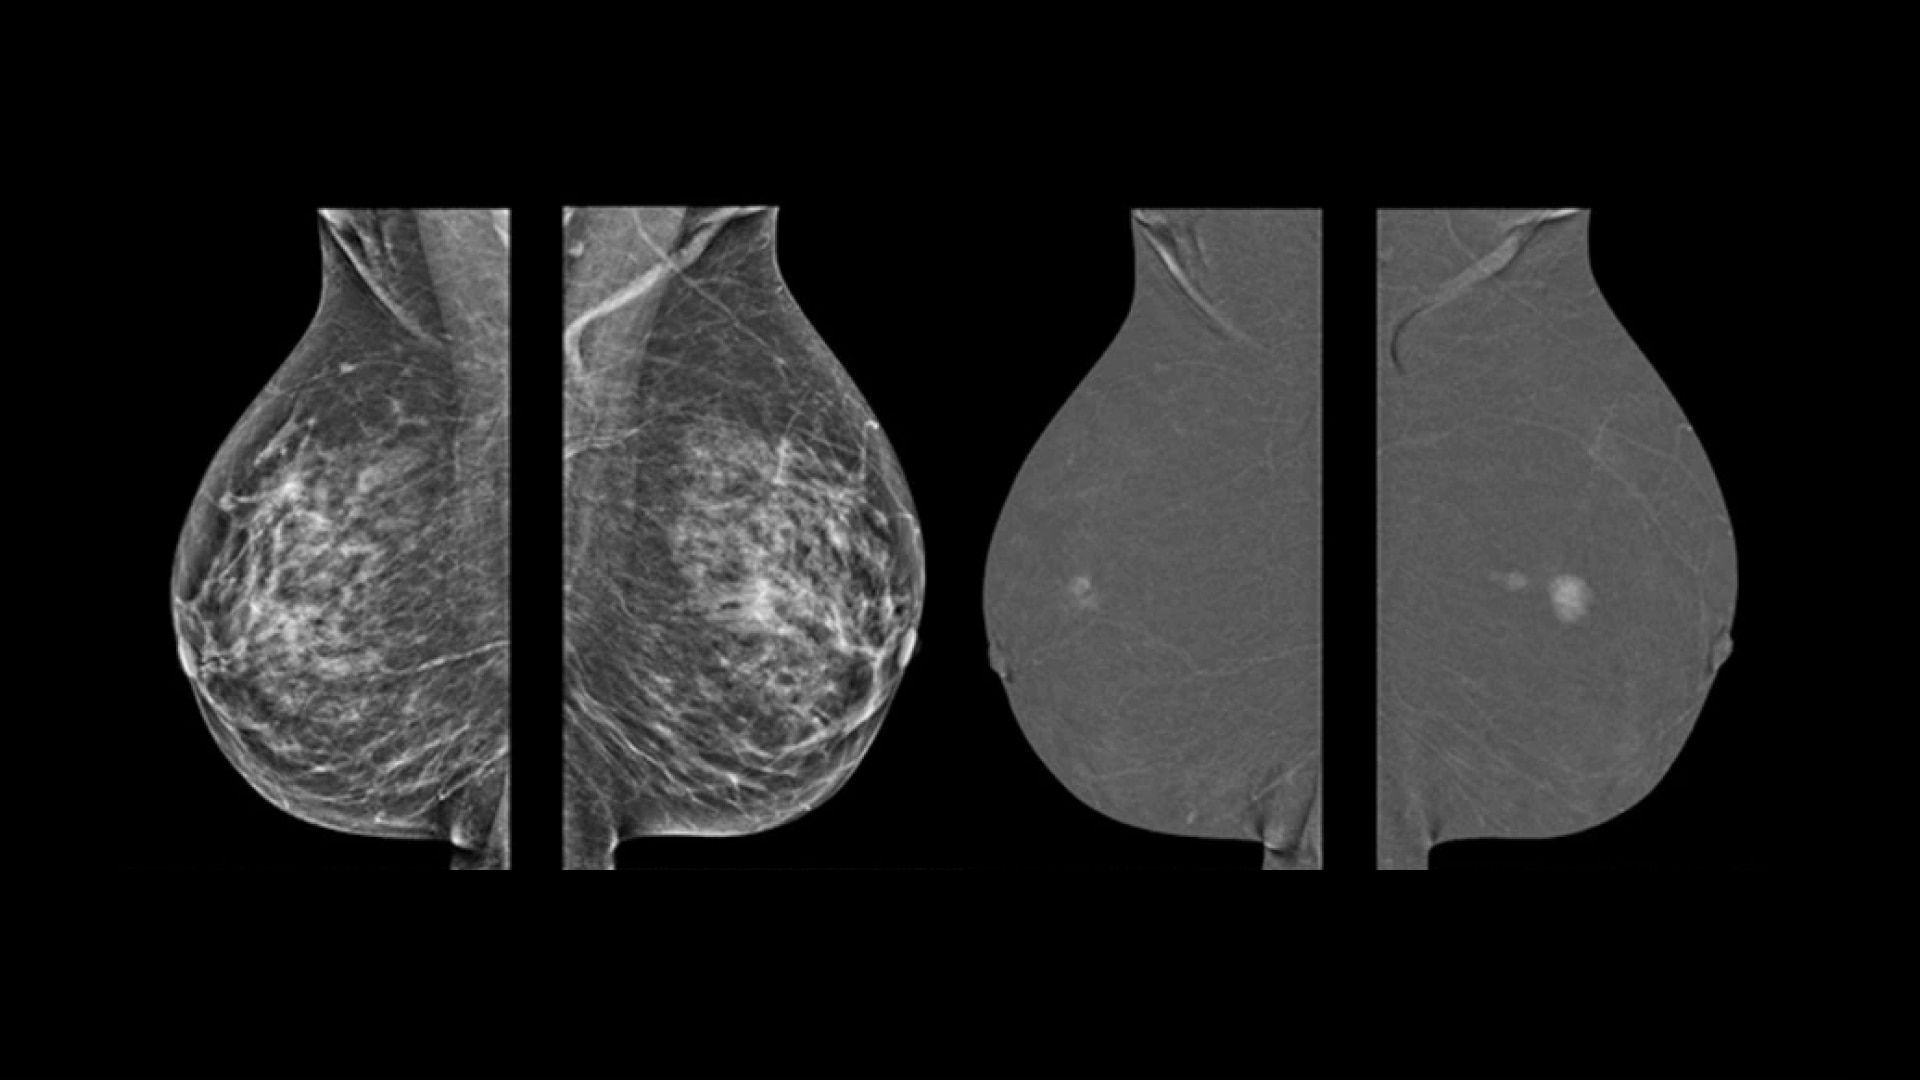

• Helps reduce the masking effect of fibroglandular breast tissue and increases the tumour signal1.

• Contrast agent highlights areas of unusual blood flow.

• Find lesions that cannot be seen on routine mammography6,7,8.

• Provide high specificity for low false-positives1.